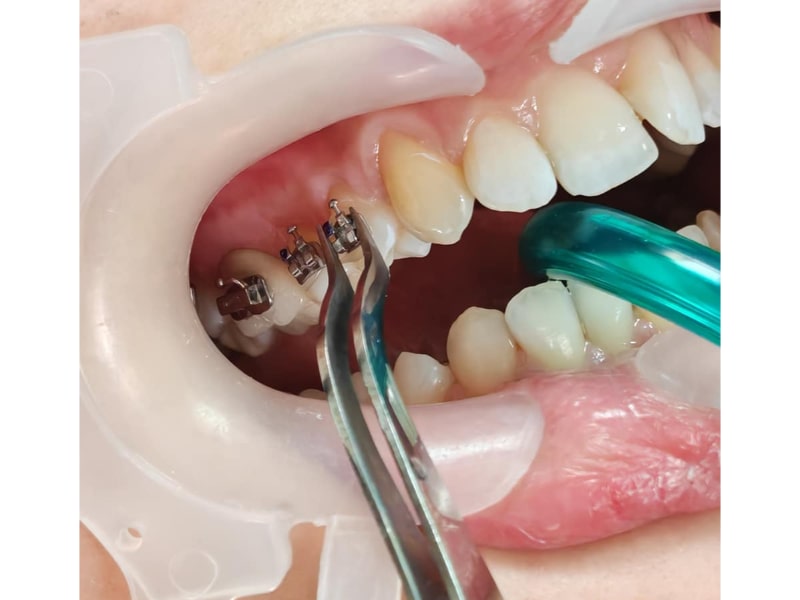

Ortodonție